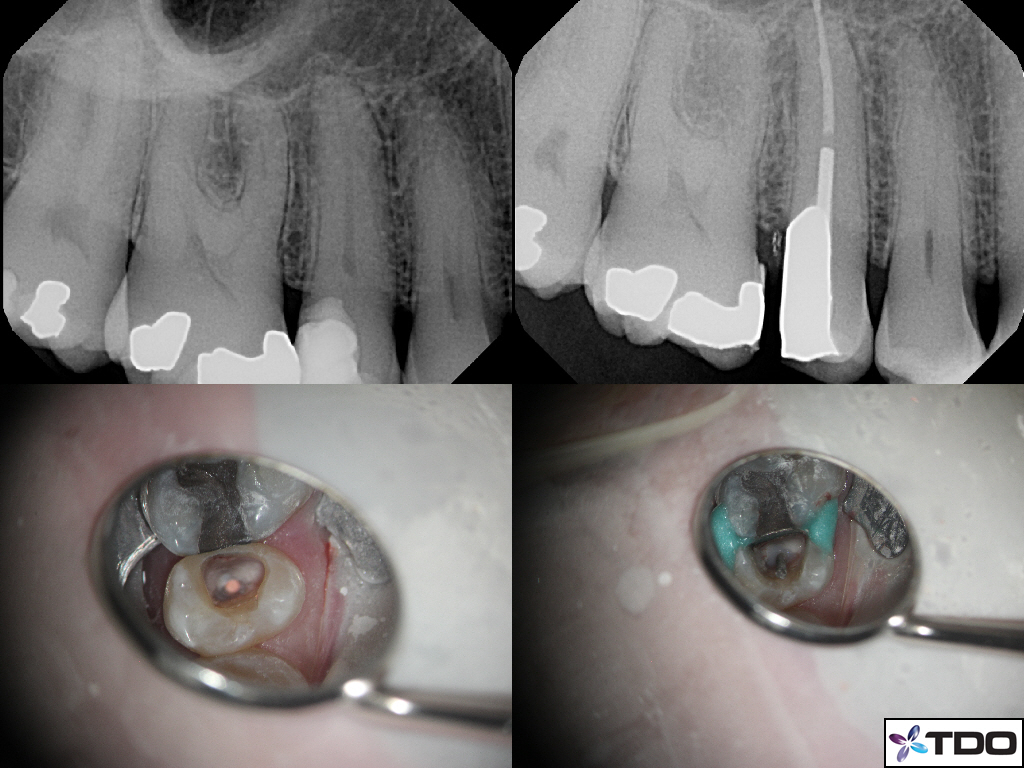

These cases show a level of commitment to conservative endodontics rarely seen in endo today. Plus the restorative excellence is inspiring and should stimulate all endodontists to up their game and help others realize how important the restorative aspect of endodontics is.